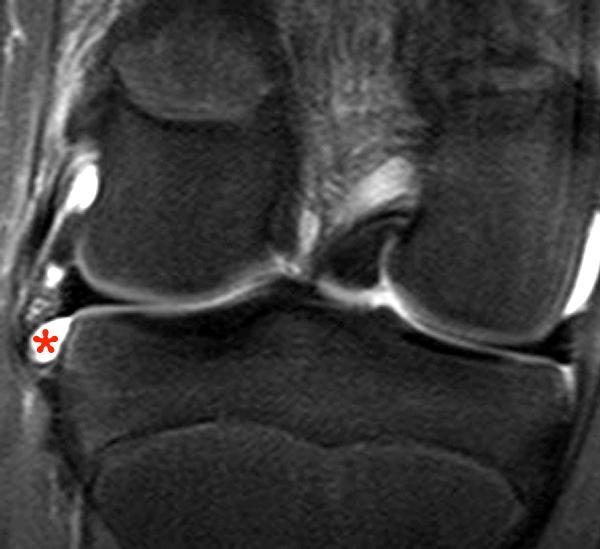

A group of fibers … Hypermobile Lateral Meniscus - Radsource

Hypermobile Lateral Meniscus - Radsource from radsource.us